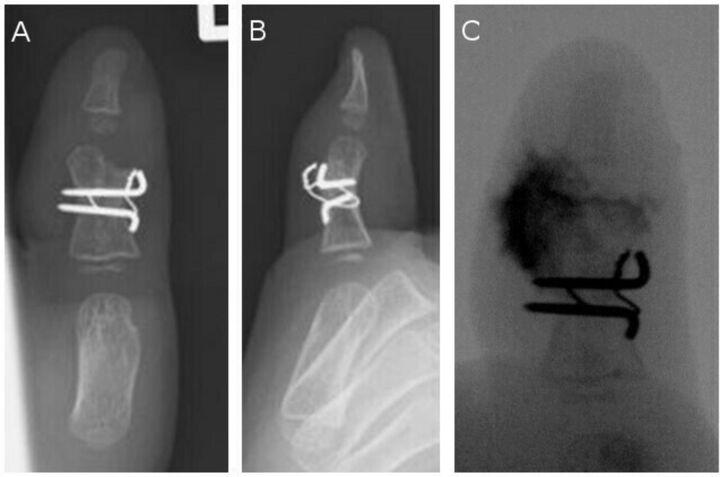

We present a case of a postoperative cartilage defect in a patient with polydactyly who was treated with a costal osteochondral graft. Excision of the radial digit and ligamentous periosteal flap with longitudinal osteotomy were performed when the patient was 1 year old. The alignment of the interphalangeal joint was straight after surgery, but the deviation gradually developed. A revision surgery using a costal osteochondral graft was performed when the patient was 3 years old. A satisfactory outcome was obtained at the 3-year follow-up. The authors suggest that a costal osteochondral graft may be a reasonable option for revision surgery for a postoperative cartilage defect.

我们报告了 1 例多指术后软骨缺损患者的病例,该患者接受了肋软骨骨软骨移植治疗。当患者 1 岁时,进行了桡侧指切除和韧带骨膜瓣的纵向骨切开术。术后指间关节对线笔直,但逐渐出现偏斜。当患者 3 岁时,进行了使用肋软骨骨软骨移植的翻修手术。3 年随访时获得了满意的结果。作者认为,肋软骨骨软骨移植可能是术后软骨缺损翻修手术的合理选择。